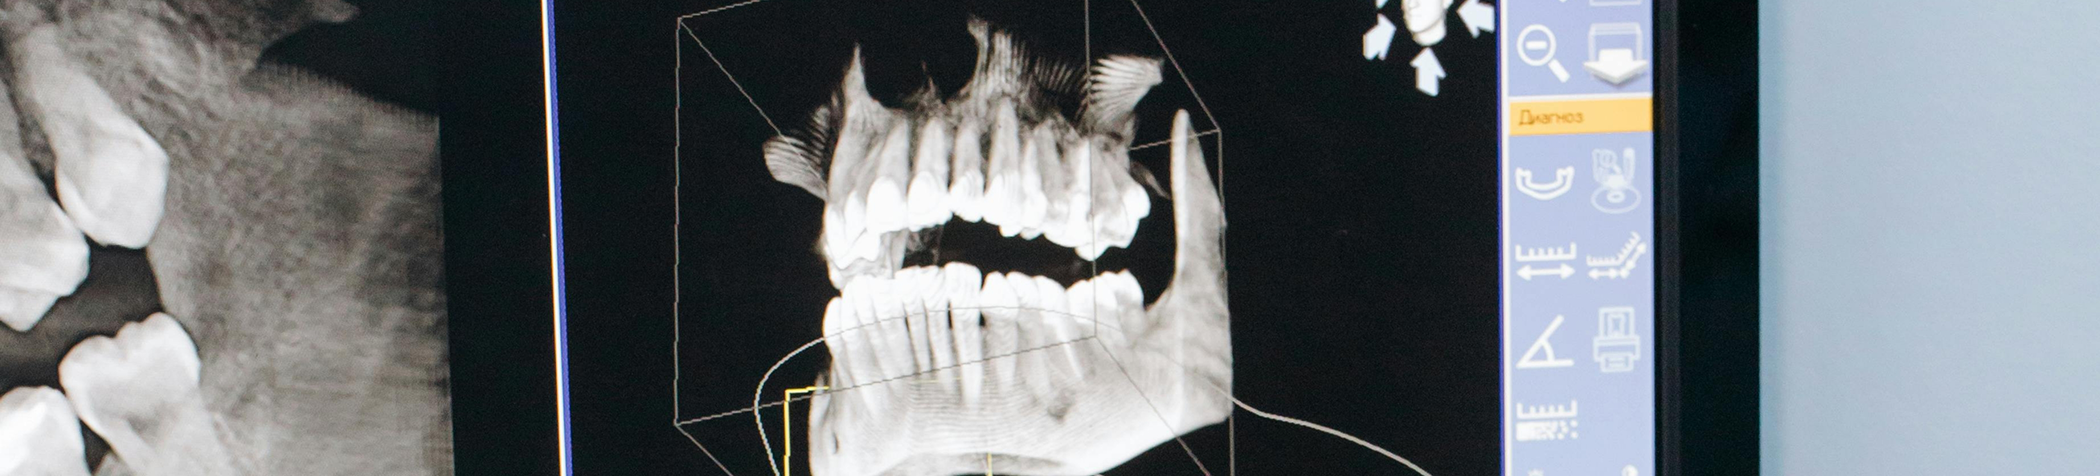

CT/ Cone Beam Scanner

Our VaTech Green CBCT Scanner is an innovative piece of imaging technology designed to produce a three-dimensional model of a patient’s head and mouth. Using hundreds of scans, which are captured with its 360-degree rotating arm, unique software formulates a 3D image that displays the various nerve pathways, blood vessels, teeth, jawbone, oral tissues, etc., that are necessary for treatment planning.